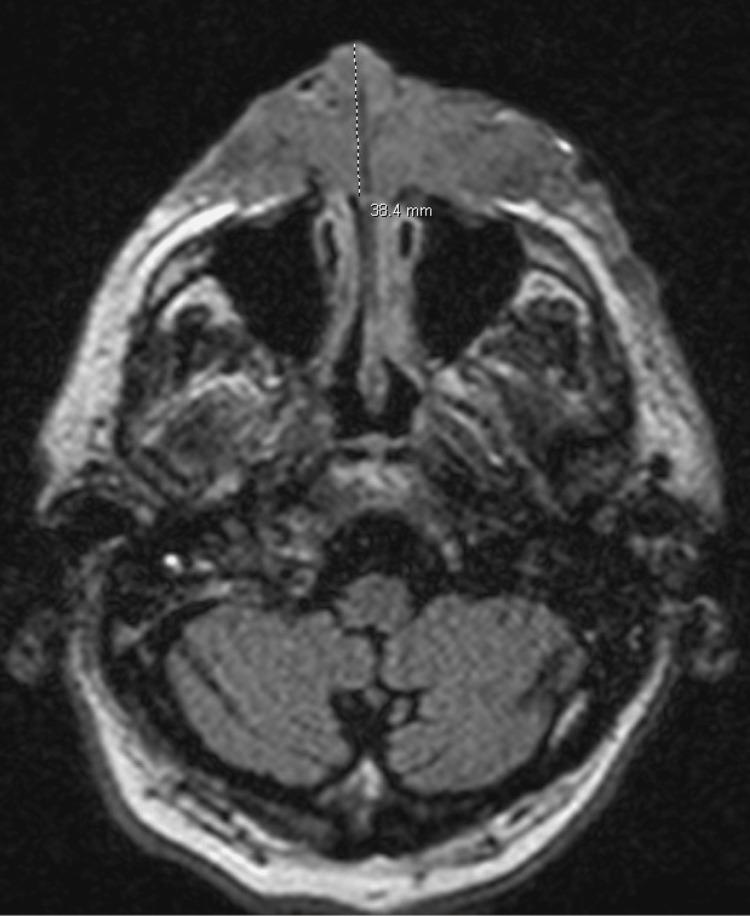

Nodular melanoma is an aggressive subtype of malignant melanoma, accounting for a disproportionate number of melanoma-related deaths due to its rapid progression and early metastatic potential. Despite its distinct histopathological characteristics, clinical diagnosis can be challenging, particularly when the presentation mimics other conditions. We present the case of a 67-year-old male whose facial nodular melanoma was initially treated as an invasive fungal infection due to overlapping clinical and radiographic features, including osseous destruction, soft tissue invasion, and systemic involvement. The patient underwent antifungal therapy, which resulted in acute kidney injury from amphotericin B, prior to a definitive diagnosis by histopathological analysis. This case highlights the importance of maintaining a broad differential diagnosis for atypical facial lesions, especially those with aggressive features or poor response to initial therapies. Early biopsy and tissue evaluation are essential to distinguish malignant melanoma from infectious or inflammatory conditions and to ensure timely, appropriate management.

结节性黑色素瘤是恶性黑色素瘤的一种侵袭性亚型,因其进展迅速和早期转移潜能,在黑色素瘤相关死亡中占比过高。尽管其具有独特的组织病理学特征,但临床诊断可能具有挑战性,尤其是当临床表现与其他疾病相似时。我们报告一例67岁男性病例,其面部结节性黑色素瘤最初因临床和影像学特征重叠,包括骨质破坏、软组织侵犯和全身受累,而被当作侵袭性真菌感染进行治疗。在通过组织病理学分析明确诊断之前,患者接受了抗真菌治疗,该治疗导致了两性霉素B引起的急性肾损伤。该病例强调了对非典型面部病变保持广泛鉴别诊断的重要性,尤其是那些具有侵袭性特征或对初始治疗反应不佳的病变。早期活检和组织评估对于区分恶性黑色素瘤与感染性或炎症性疾病以及确保及时、恰当的治疗至关重要。